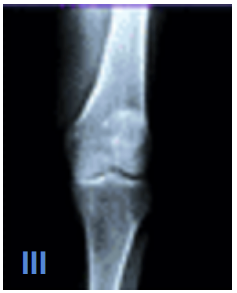

What are some of the characteristics of Kelgren and Lawrence Level III OA?

A

Moderate reduction in joint space

How well did you know this?